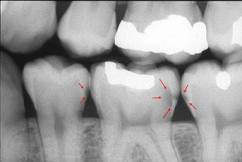

El ICCMS clasifica radiográficamente las superficies

posteriores de los dientes (36,37) Se

ha reportado que tanto la reproducibilidad como la precisión

de este sistema de clasificación son de significativas (33)

a excelentes (37)

La evidencia

indica que la profundidad de penetración radiográfica en la

que se puede predecir de forma confiable que la superficie

del diente está cavitada y que la dentina está muy

infectada, es cuando la radiolucidez está más alla del

tercio externo de dentina (7,34,35,38,40).

Esto corresponde a los códigos 4, 5 y 6 en el sistema de

clasificación radiográfica de ICCMS. Ver tabla 6. En casos en que las

tasas de progresión son rápidas, se puede esperar que en

lesiones con clasificación 3 en el sistema descrito

anteriormente, haya formación de cavidad.